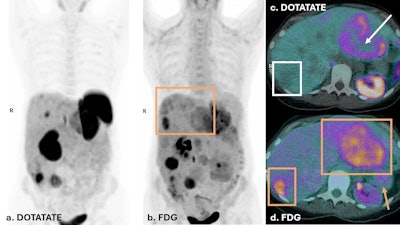

Dual PET imaging in Case Two illustrates a patient with discordant disease. FDG PET (b & d) shows FDG uptake in tail of pancreas primary lesion (yellow arrow), as well as multiple hepatic metastases (yellow boxes), with enlarged liver span. DOTATATE PET on left (a) shows several hepatic metastases that do not demonstrate DOTATATE uptake above background of liver parenchyma. The liver lesions in (c) demonstrate moderate FDG uptake in liver lesions, with no corresponding DOTATATE avidity (white box) or central photopenia (white arrow). This discordance in dual PET imaging corresponds to a NETPET score of 5. This suggests de-differentiated disease and a less favorable prognosis. The patient was not suitable for Lutate treatment and received chemotherapy.

A 45-year-old woman was diagnosed with metastatic grade 2 pancreatic NET in 2021. Dual PETs showed discordant disease with multiple FDG-avid, non-DOTATATE-avid hepatic metastases (NETPET score 5). She started chemotherapy and lanreotide treatment. Restaging dual PETs showed a mixed response, with reduced size of the pancreatic primary but increased FDG avidity in the liver (NETPET score 5).